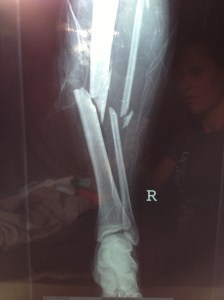

This is my running history, I started running in California when I was young and continued on in to high school. It is there where I learned and loved to compete. With my fastest time in the 1500 being 4:47 I was looked at by many universities. But unfortunatley at this time I was starting to feel burnt out from running and started seeing my times increase. So to avoid the pressure of any big university I chose to run for a junior college instead. After about a year of attending the junior college I decided to move to Utah to continue my education. I continued to run but not competitivley. I continued to feel sluggish as I did that senior year of high school. Then on Christmas day of 2001 driving home from work from the local ski resort I was in an accident. Heading down the canyon I drove over black ice that spun my Honda Civic out of control into the middle mediam. The impact force then caused my car to slide across the road on to the shoulder hitting the gaurd rail. Although, the momentum was great enough to rip the rail out if its anchors and it folded on its self. This caused a strengthing effect and the doubled up metal pushed through the front passenger side and out through the drivers door. The guard rail tore through the door of the Civic and out the otherside taking the seats with it. Miraculously leaving only one piece of precious cargo, ….me. Once the enertia ceased I was left sitting on top of the doubled up guard rail pinned against the steering wheel, legs caught between the clutch and the brake. It was truly a miracle I survived. The damage, although for me a runner was very serious, was very minimal and superficial. The trauma included the tearing of all ligaments in the left knee, two broken legs with one major compound fracture.

As one could imagine, this put my running on hold. I was hospitalized for two weeks followed by four months of being wheelchair bound not to mention the massive rod hammered into my right leg.